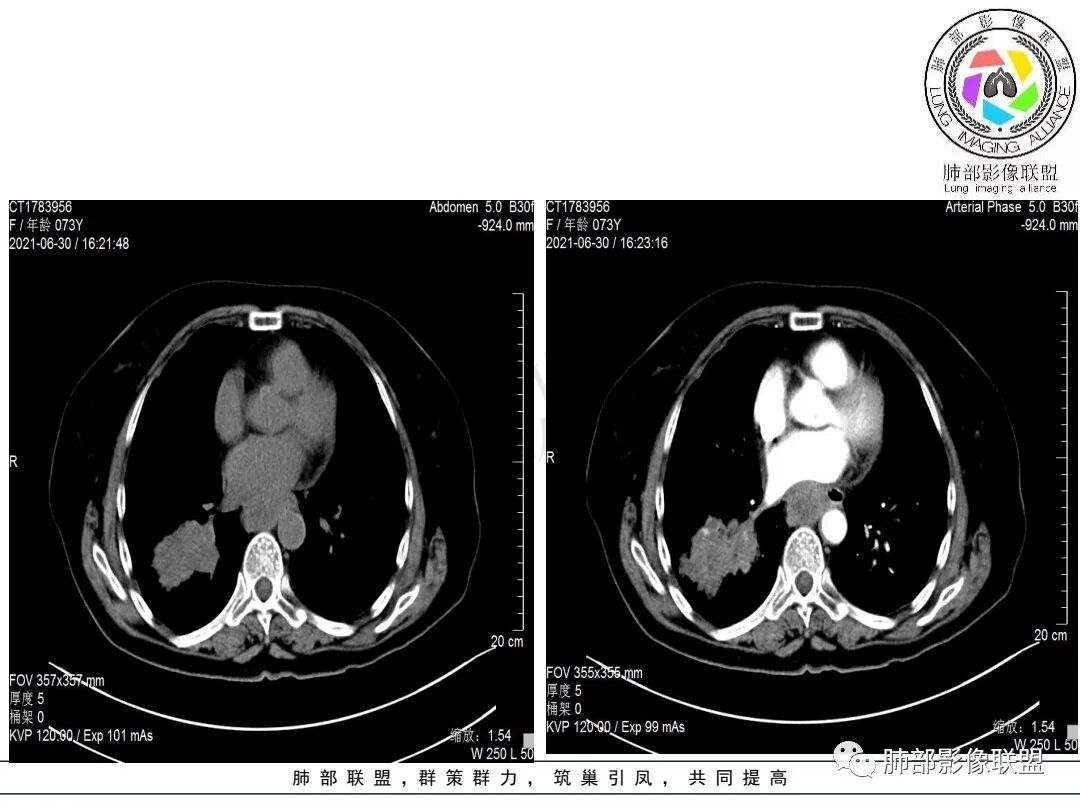

考虑小细,纵膈及右侧肺门淋巴结肿大并左下肺小叶间隔增厚,提示周围及中央淋巴管转移,左心房及左下肺静脉受累。

老年女性,右肺下叶沿支气管走形肿块,背段支气管阻塞,密度不均,7区及肺门肿大淋巴结,前者侵及左心房,考虑恶性,小细胞?鳞癌?

纵隔淋巴结肿大明显,对邻近左心房有侵犯,右肺下叶肿块类指套征,定性恶性,右肺下叶肿块强化不明显,cea不高,猜小细胞癌或混合癌

胸部CT:桶胸,肺气肿背景,右下肺不规则肿块影,沿支气管血管束生长,边界较清,边缘毛糙、锯齿样,基底干支气管腔内隆起,部分支气管进入后堵塞。平扫密度较均匀,轻度强化,肿块内血管增粗模糊,7区淋巴结肿大明显,内见小片坏死,左房受侵,邻近胸膜增厚。考虑恶性,低分化腺?鳞?鉴别TB、PC等。

轻度不均匀强化,病灶内小血管显示不满意,未见明确坏死区。

4.右肺门及纵隔见多处增大淋巴结,不均匀环形强化,后下纵隔(隆突下)肿大淋巴结十分显眼!

3)病灶强化不显著,支气管相关,纵隔淋巴结肿大明显,小细胞癌的可能性是比较大的。黄勇老师曾统计后下纵隔(隆突下)显著肿大淋巴结,小细胞癌占比相当高,临床实践也是如此。